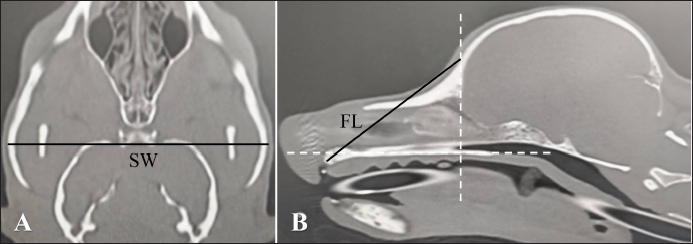

Next, individual differences in nose length were investigated. Different breeds have different nose lengths. In addition, the nasal structure can vary based on the skeletal structure. Thus, the nose length was calculated in this study, and the correlation between nose length and air percentage or contrast enhancement was examined in each breed. Two methods were used to calculate the nose length. One is the facial index (FI), a kind of cephalic index (Andreis et al., 2018; Miles and Schwarz, 2020). Although actual measurement values obtained from a skeletal specimen are originally used in this method, this study used , which resulted from measuring distances at equal parts after identifying those parts on CT images. was calculated as follows:

where skull width (SW) is the length between the most lateral points of the zygomatic arch (dorsal section, Fig. 2A) and FL is the length between the nasion and the prosthion (sagittal section, Fig. 2B).

Fig. 2. A and B. CT measurements for FIct. A: SW: the length between the most lateral points of the zygomatic arch (dorsal section). B: FL: the length between the nasion and the prosthion (sagittal section). Window width: 5,000, window level: 1,000.